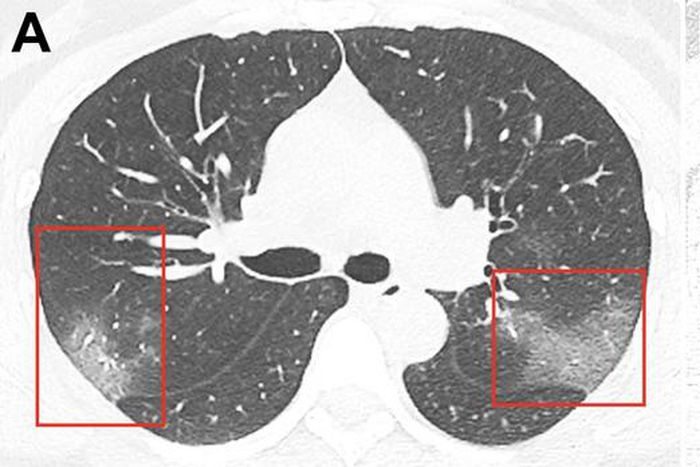

Coronavirus patient chest x ray